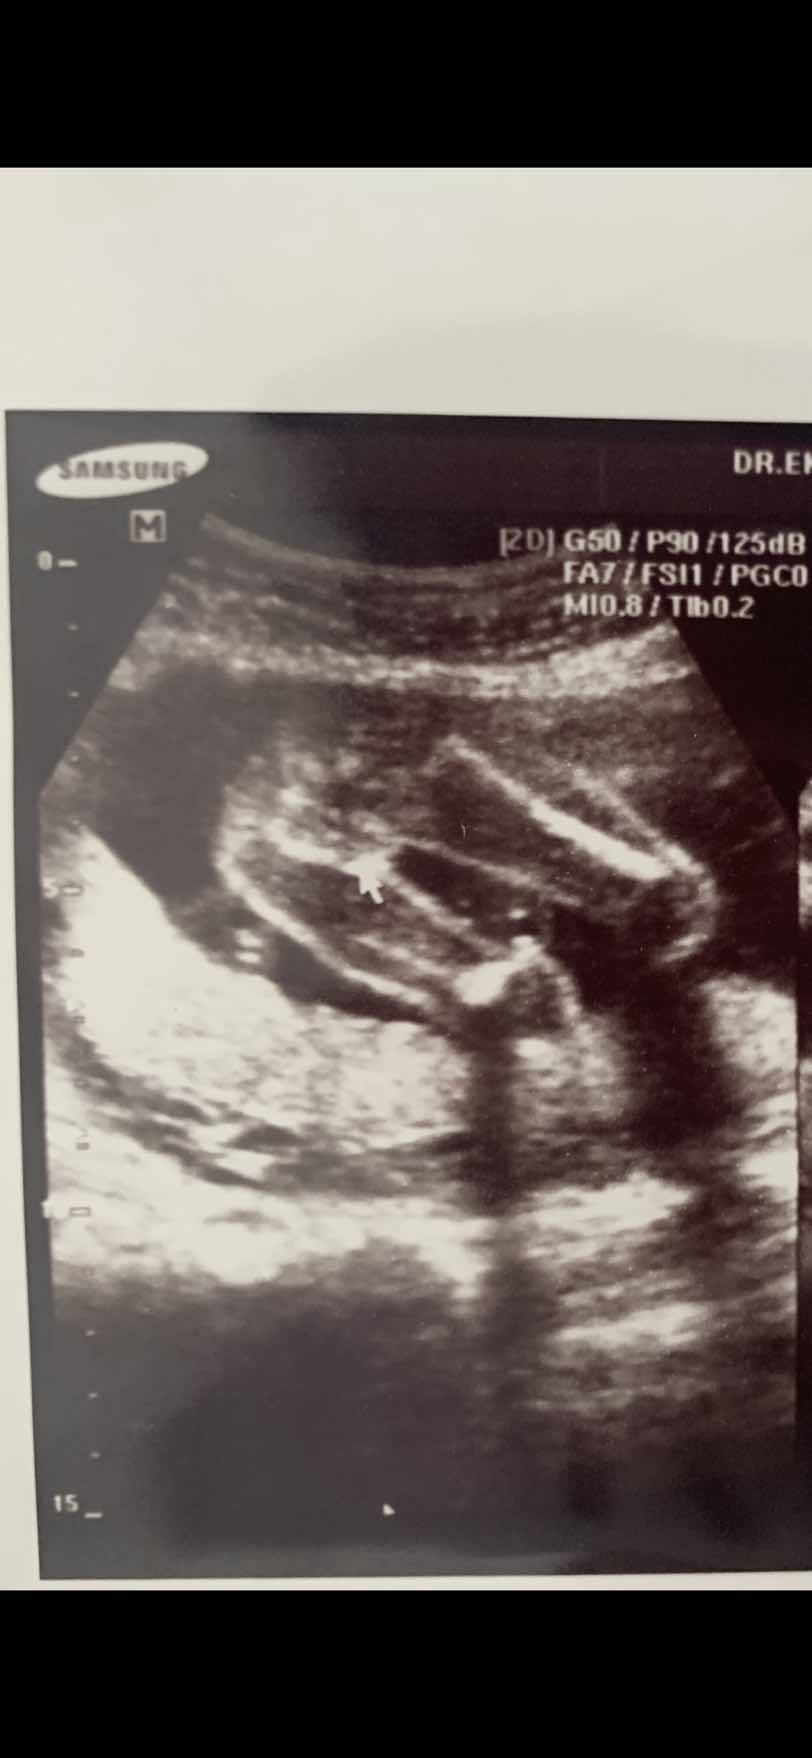

ขอดู รูปซาว หน่อยค่ะว่าเหมื่อนกันไหม หมอ บอกว่า เป็น ญ เพราะไม่มีจู๋โผลมา บ้านอื่น ได้ ญ แบบนี้หรือเปล่าค่ะ แม่แอบกังวล อยากได้ญ กลัว จู่ โผล่มาทีหลัง 😁23+4.

หมอบอกผู้ชายจ้ามีไข่มีจุ๊ดจู้🤣รอลุ้นอีกทีค่า